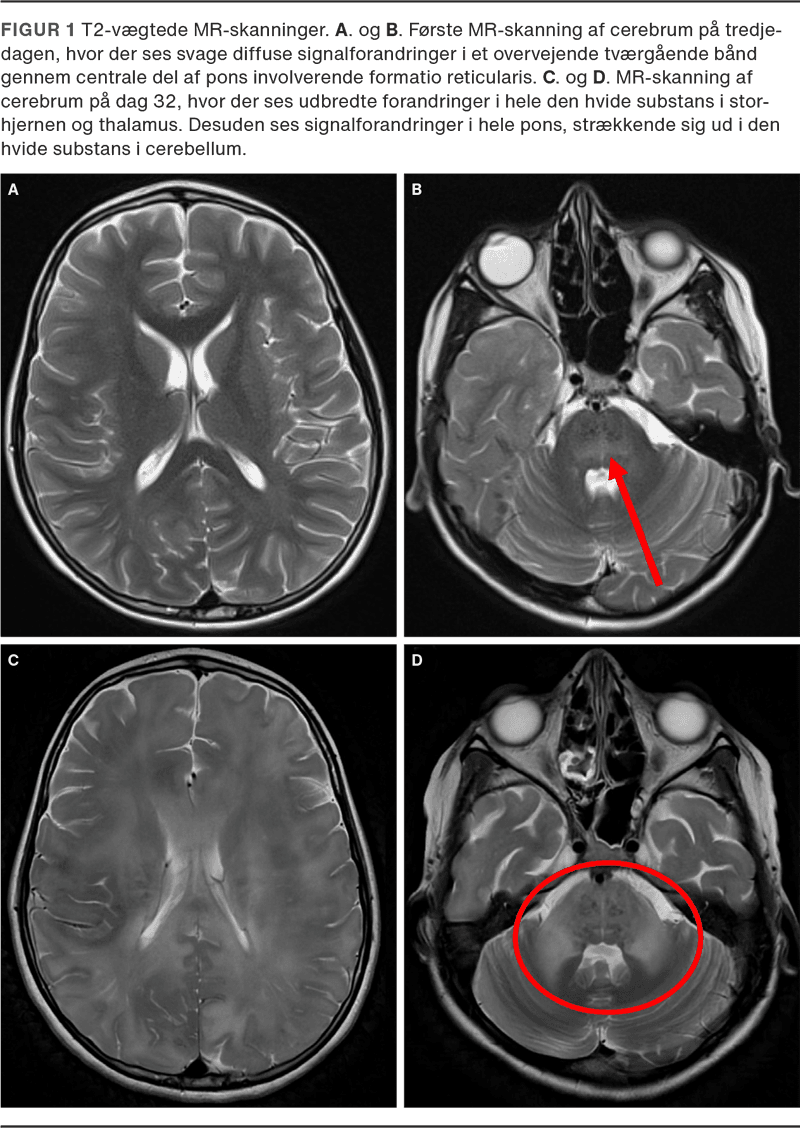

Efter indlæggelsen blev drengen tiltagende bevidsthedspåvirket og udviklede cerebral irritabilitet. Glasgow Coma Scale (GCS) faldt til fem i løbet af 48 timer, og drengen blev intuberet. En lumbalpunktur viste 9 × 106/l (fys < 3 × 106/l) leukocytter og 0,6 g/l (0,15-0,45 g/l) protein i cerebrospinalvæske (CSV), og en PCR-analyse for standard meningitpanel var negativ. Akut MR-skanning af cerebrum viste svage diffuse signalforandringer i den centrale del af pons involverende formatio reticularis og gav mistanke om akut dissemineret encefalomyelit (Figur 1).

MR-skanning af cerebrum på dag 32 viste betydelig progression (Figur 1). CT af cerebrum viste stigende intrakranielt tryk. Neuroprotektivt regime blev iværksat, og på vital indikation forsøgtes rituximab.